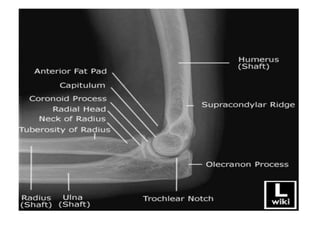

ELBOW

AP & Lateral

• Appearance(Years)

• 1st- Capitulum and lateral

part of trochlea

• 5th – Head of Radius

• 6th- Medial epi. Of

humerus

• 9th- Medial part of

trochlea

• 10th- Top of Olecranon

process

• 12th- Lateral epi. Of

Elbow • Appearance(Years) • 1st-Capitulum and lateral part of trochlea • 5th – Head of Radius • 6th- Medial epi. Of humerus • 9th- Medial part of trochlea • 10th- Top of Olecranon process • 12th- Lateral epi. Of humerus • Fusion • 15th- Olecranon epiphysis with upper end of ulna • 16th – lateral epicondyle, capitulum and trochlea into one mass, and with shaft. • 17th- Head of radius to shaft • 20th – Medial epicondyle of humerus to shaft